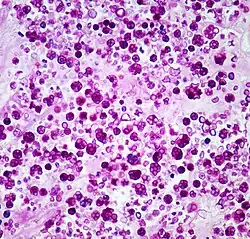

Histologic stain of a Prototheca zopfii infection in a dog